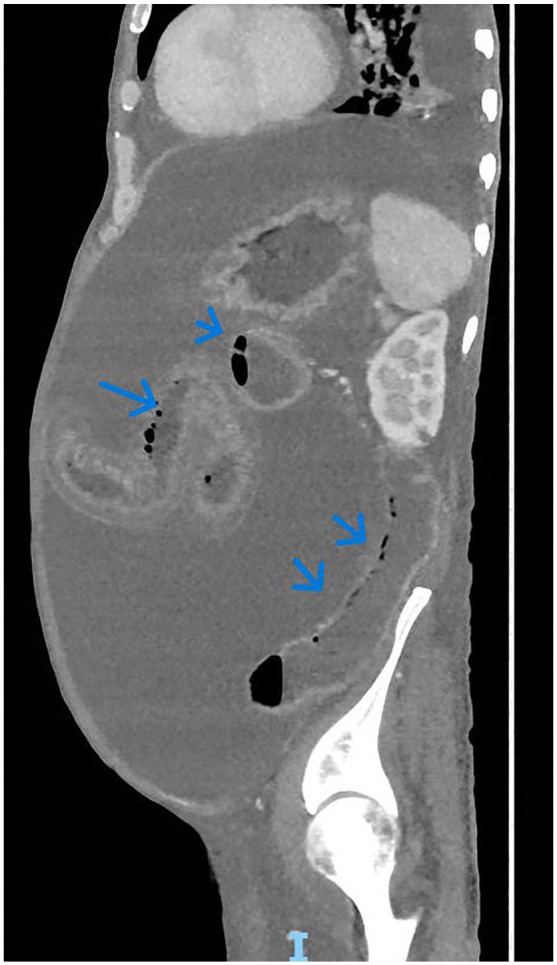

Pneumatosis intestinalis (PI) is characterized by the presence of air within the walls of the small intestine, large intestine, and sometimes the gastric wall. The mechanism and pathogenesis of PI are poorly understood. The discovery of PI can occur in the form of an incidental finding, such as a benign course or a life-threatening condition, such as intestinal ischemia. Point-of-care ultrasonography (POCUS) for pneumatosis intestinalis (PI) is rarely reported in adults, with only 1 previous poster presentation. However, POCUS is well-documented in the pediatric population, particularly for the diagnosis of intussusception. We present a 78-year-old man with longstanding uncorrected severe pulmonary stenosis, right-sided heart failure, atrial fibrillation on dabigatran, diabetes, and cirrhosis who presented with progressive abdominal distension. POCUS and computerized tomography of the abdomen showed ascites, diffusing small-bowel wall thickening with edema, and pneumatosis intestinalis, without portal venous gas or vascular occlusion. Patient was transitioned to palliative care on diuretics, lactulose; follow-up ultrasound showed only mild ascites but persistent small-bowel PI. This case report marks the second instance of POCUS being utilized for PI in an adult population. POCUS can play an essential diagnostic role at the bedside, ruling out serious underlying etiologies and guiding physicians in further diagnostic testing.